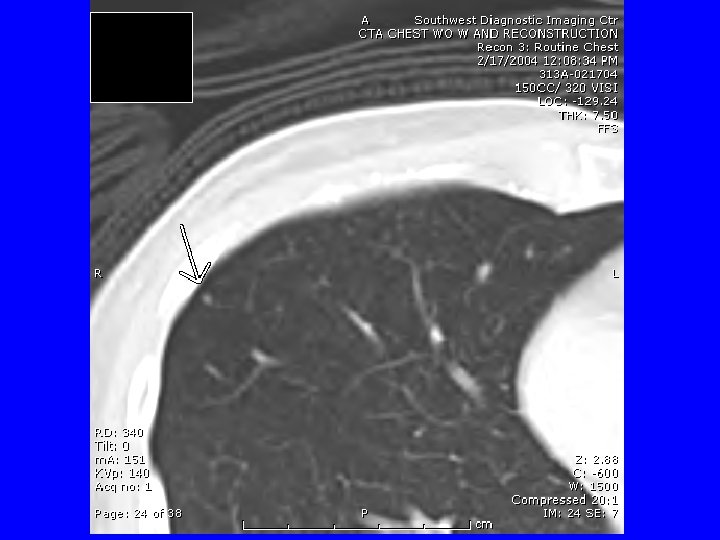

CTA if another episode. She called the next day after a worse episode of tightness, SOB, and hemoptysis. CTA 2/17/04 “tree in bud bilateral and diffuse” suggesting infection or inflammation. Bronchoscopy 2/18/07 appeared normal, with biopsies revealing “mild chronic inflammation. ” March 4 received report of outpatient sputum growing an AFB, and I assumed MAC, and discussed Abx therapy. She then decided on VATS OLBx. (Bronch and OLBx cultures were both negative ultimately. )

HP -CT Findings • • • Ground glass opacities Poorly defined centrilobular nodules Mosaic attenuation on inspiration Air trapping on expiration Reticulation (fibrosis) when chronic Silva CI, Churg A, Muller NL. Hypersensitivity pneumonitis: spectrum of highresolution CT and pathologic findings. Am J Roentgenol 2007; 188: 334 -44.